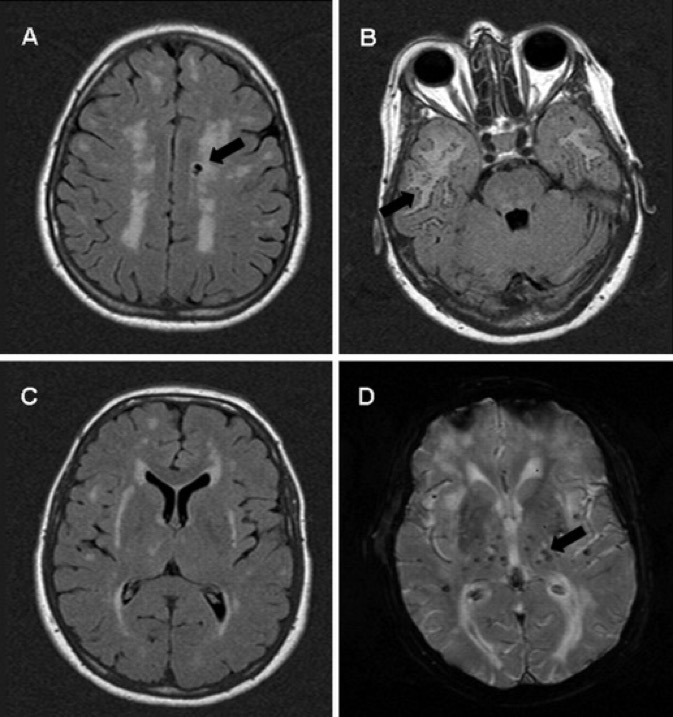

Axial FLAIR (A–C) and T2*GE (D)

- hypersignaux confluents (A–C)

- infarctus lacunaires (A, flèche)

- lésions lacunaires sous-corticales (B, flèche)

- microsaignements (D, flèche).